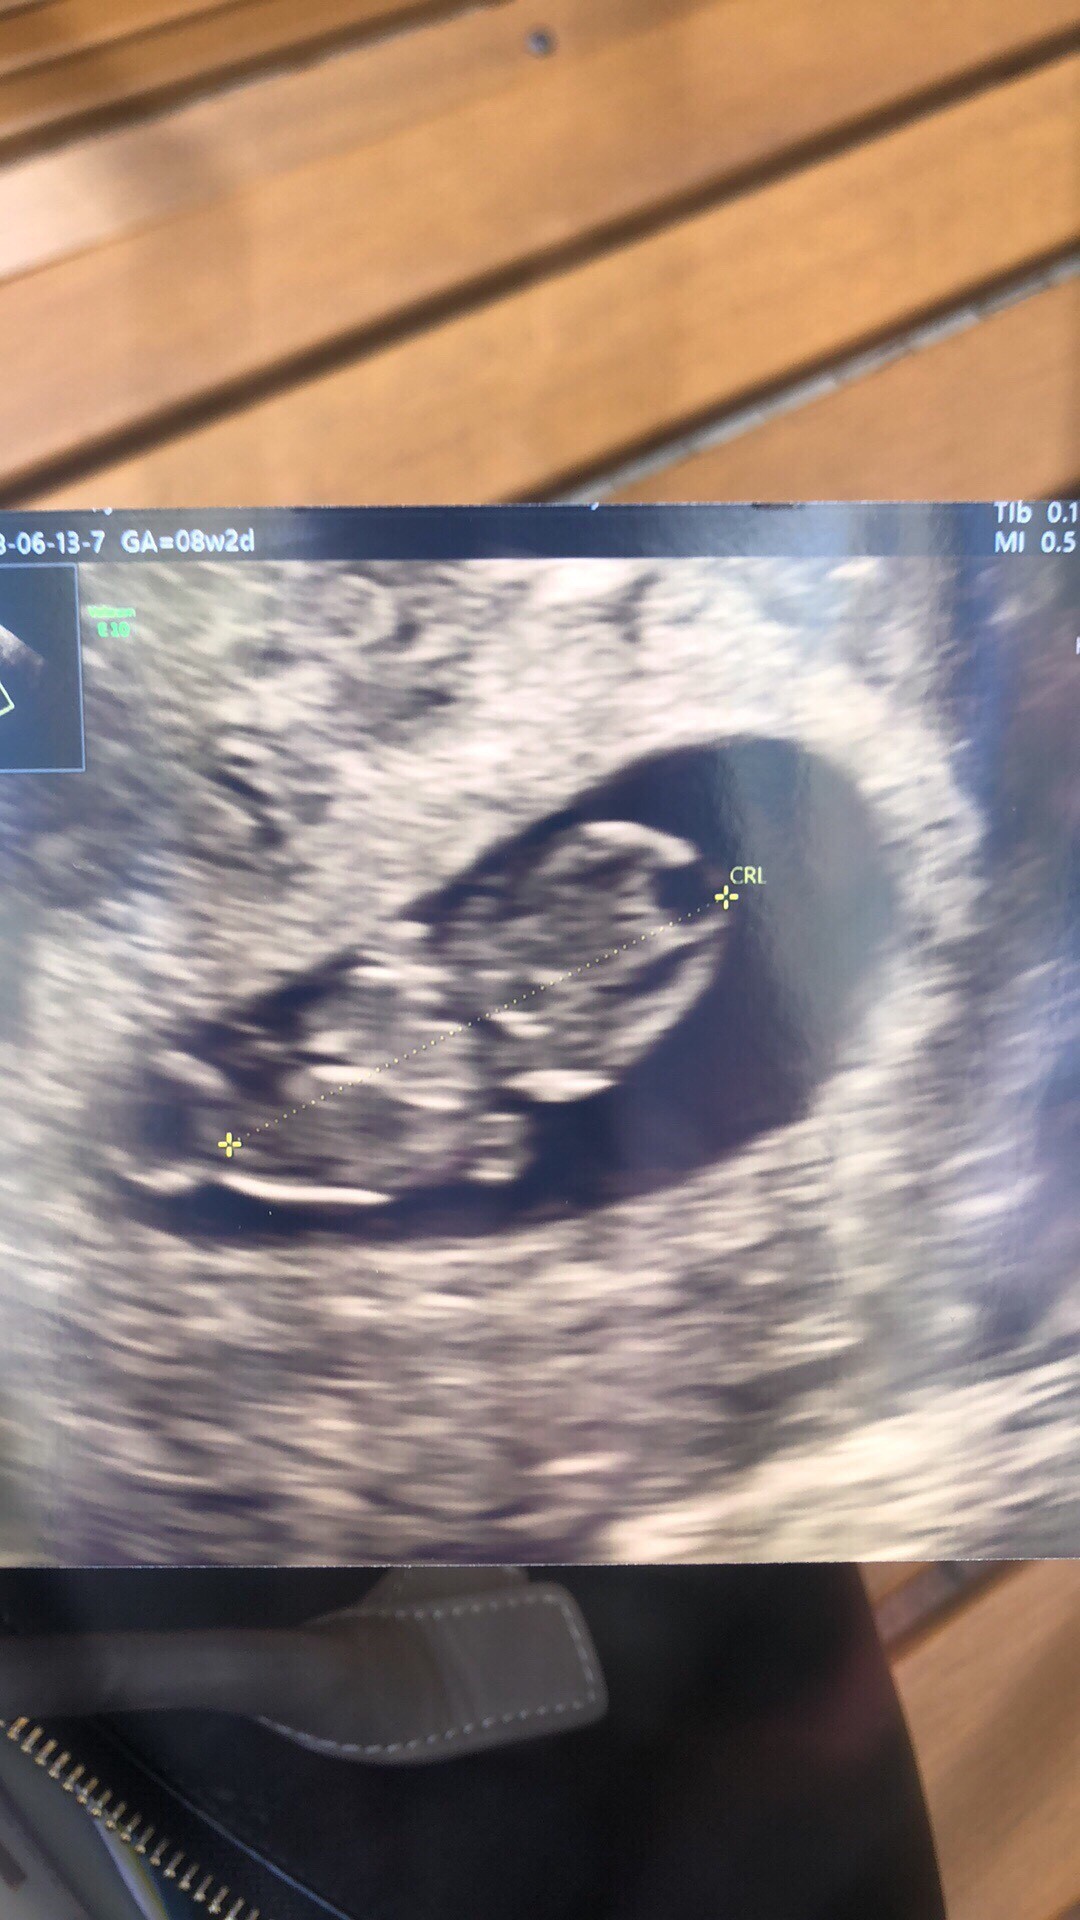

U nas prawie 2 cm człowieka, serduszko bije, nawet ruszał rączkami :) coś tam mi się podobno odkleja, ale nie przy kosmowce wiec nie ma żadnego zagrożenia dla dziecka i powinno się przykleić z powrotem. Termin porodu z usg w sama niedziele wielkanocna :) 21.04.

I jeszcze zdjęcie :)